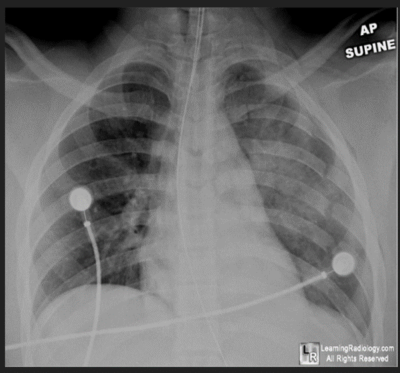

Radiograph of a 10 yr old boy who presented with shortness of breath which had become progressively worse over 48hrs. Which is true

What radiological finding is shown in this x-ray picture:

What x-ray Feature is shown

Classical feature seen on this X-ray